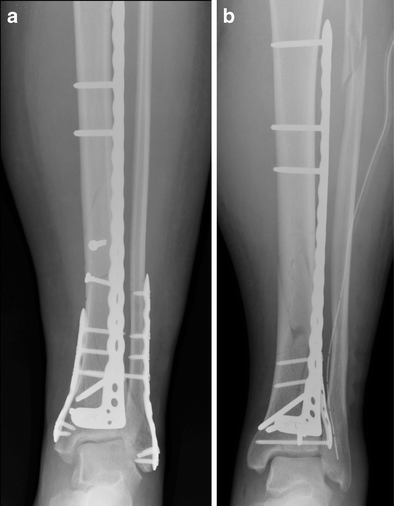

a Post-operative, AP X-ray of a patient aged 45 years after AO 43-C1 fracture treated with anatomical anterolateral locking plate fixation with additional lag screws (rigid fixation). b Post-operative, AP X-ray of a patient aged 51 years after AO 43-C3 fracture treated with anatomical anterolateral locking plate fixation without use of lag screws